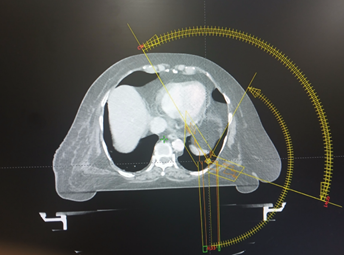

Plans were calculated with 6MV FFF (Figure 3).

Figure 3. Arc offsets (use of 3 arcs, including a

partial arc).